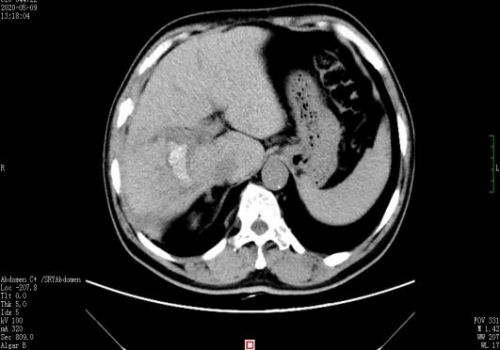

术后复查ct示结石已取尽。

术中情况如术前判断,腹腔内致密粘连,解剖结构难辨;肝方叶肥大增生,胆管狭窄亦为敞开肝门增加了很大难度。在胆道外二科专家团队的高超技艺和谨慎操作下,运用特色硬镜联合钬激光碎石方法,结合胆管高位切开及胆管微整形技术,在保肝的情况下清除肝内外胆管结石。手术历时3个小时顺利完成,术中无输血。术后复查肝内胆管结石全部取尽。

手术后,胆道外二科医护人员运用加速康复外科ERAS理念,采用多模式镇痛、早期鼓励患者开展机体功能锻炼等措施。术后第二天,患者即进流食,下床活动;术后第三天复查CT显示,肝内胆管结石已全部取尽,王先生向医护人员竖起大拇指连连称赞。(胆道外二科:胡霞红 米杨 )